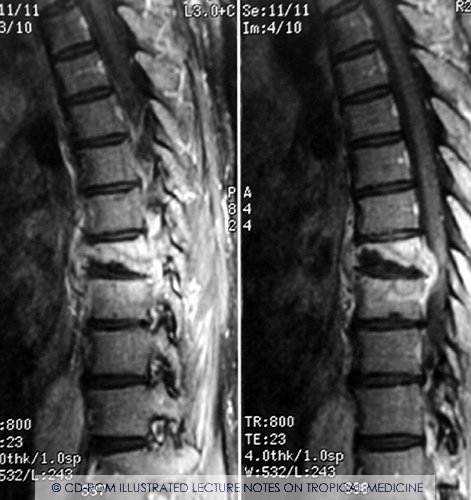

Spine TB